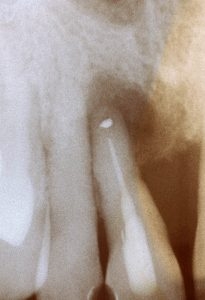

| 2017 | Bröseler F. Regenerative Parodontitistherapie - ein Praxiskonzept Quintessenz 2017;68(4):389-394 |

![]() |